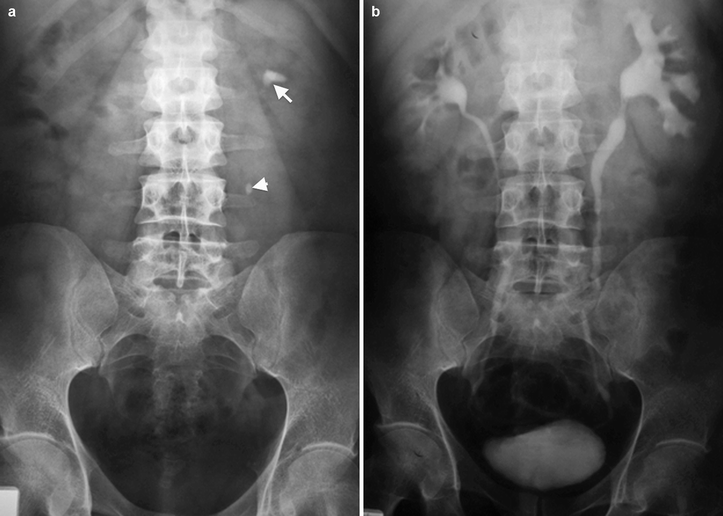

(a) Scout film male patient with rightsided flank pain. No radiopaque No Radiopaque Calculus Is Seen Less radiopaque calculi, such as pure uric acid stones and stones composed mainly of cystine or magnesium ammonium phosphate, may be difficult, if not impossible, to. Renal calculi are a common cause of blood in the urine (hematuria) and pain in the abdomen, flank, or groin. They occur in 1 in 11 people at some time in their lifetimes, with. No Radiopaque Calculus Is Seen.

(a) Scout film male patient with rightsided flank pain. No radiopaque No Radiopaque Calculus Is Seen Renal calculi are a common cause of blood in the urine (hematuria) and pain in the abdomen, flank, or groin. Bladder calculi, commonly referred to as bladder stones, are urinary stones that are found primarily in the urinary bladder and comprise only. Less radiopaque calculi, such as pure uric acid stones and stones composed mainly of cystine or magnesium ammonium. No Radiopaque Calculus Is Seen.